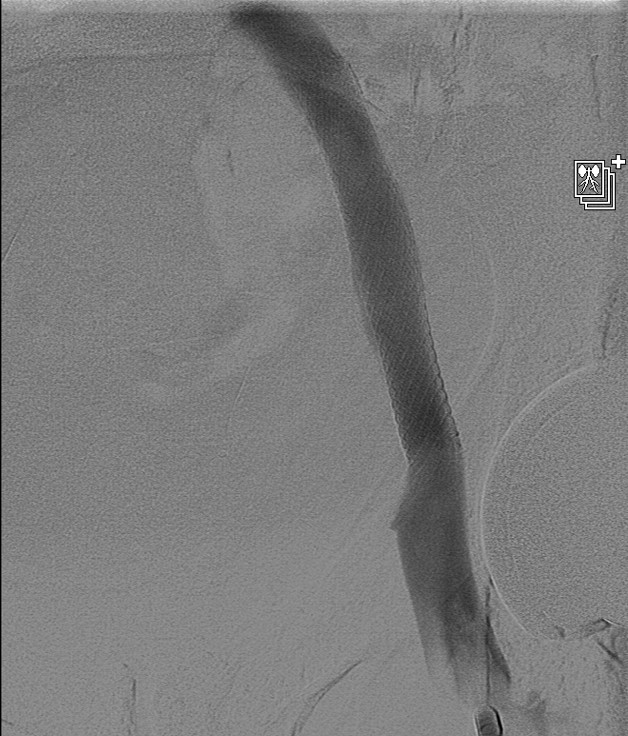

Case Presentation: A 59-year-old male patient with no significant past medical history presented to our hospital with left foot swelling that started almost four weeks prior to presentation. The swelling was progressive, ascending, and associated with erythema. The patient was initially evaluated by his primary care physician who requested a venous Doppler of his lower extremity. This was negative for deep venous thrombosis (DVT), and he was subsequently started on a course of antibiotics due to concern for cellulitis. Despite antibiotic therapy, the patient’s swelling progressed to involve the entire left lower extremity. The patient was started then on conservative venous insufficiency treatment including compression stockings, leg elevation, and later Lasix. Given the patient’s persistent symptoms and lack of improvement despite those measure, he was referred for a venogram which showed patent venous system in the right side but revealed a narrowing in his left external iliac vein, the area of stenosis occurred at the crossing of what looked like a pulsatile artery, at the level of the crossing of the hypogastric artery into the pelvis. The patient underwent angioplasty and stenting of the narrowed vein which he tolerated well. He was later discharged on aspirin, clopidogrel, and a short course of antibiotics, and his swelling resolved completely three weeks later.